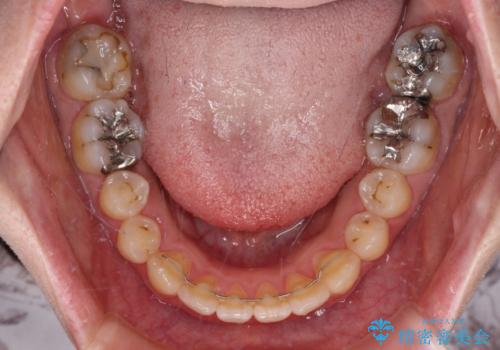

- 捻れた前歯が飛び出しており、口が閉じにくいとのことで来院された患者様です。

出っ歯というわけではないものの、前歯の捻転により口唇が押し出されている状態でした。

親知らずを抜去し、歯列全体を後方に移動させつつ、IPR(歯と歯の間を削る)でスペースを獲得し、インビザラインを用いて叢生を解消しながら前歯の突出を改善することとしました。

インビザラインは、患者様の協力無しには成立しない治療ですが、しっかりと装着時間を遵守してくださり、1年弱で治療を終えることができました。